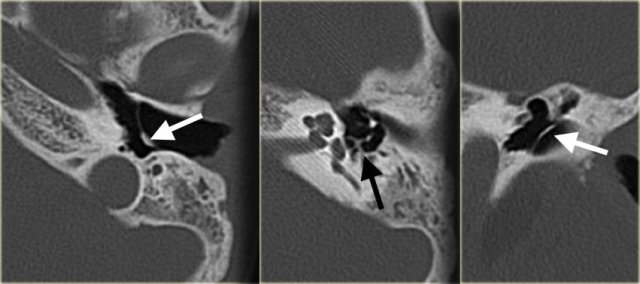

On the left a 14-year old boy.

The eardrum is thickened.

A small amount of soft tissue (arrow) is visible between the scutum and the ossicular chain but no erosion is present.

This favors the diagnosis of chronic otitis media.

On the left an 11-year old girl with bilateral ear infections.

There is calcification of the eardrum (white arrow) and calcific deposits on the stapes and the tendon of the stapedius muscle (black arrow).